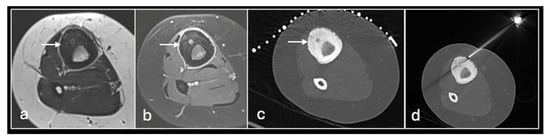

Figure 2. Axial T2fat suppressed (a), sagittal Proton density (b) showing tumour in the distal femur. Axial CT (c) showing biopsy needle in the distal femoral lesion.

We use two main needle systems. Most bone lesions can be sampled with a T-Lok eight-gauge system with an inner diamond-tipped stylet and outer cannula. This is inserted through the cortex overlying a bone lesion. Once in the lesion, the stylet is removed and the cannula is advanced to the deep wall of the lesion aiming to trap the core against normal bone on either side. A tray is then inserted through the cannula to acquire the sample. Both tray and cannula are withdrawn together and the sample is then deposited into the relevant histopathology or microbiology pots (Figure 2 and Figure 3). Typically, only one sample is needed unlike in a soft tissue biopsy.